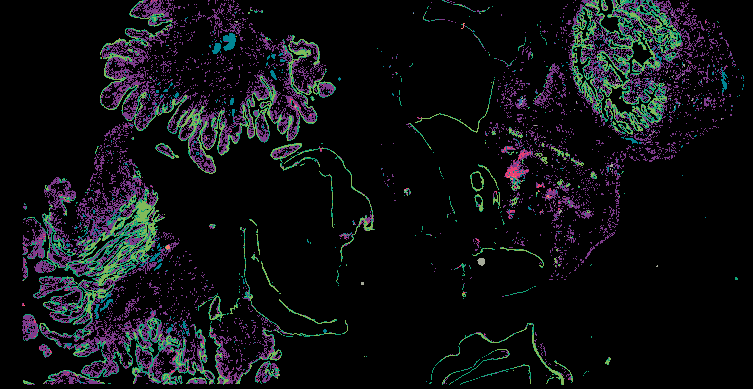

From 'Multimodal Spatial Profiling Reveals Immune Suppression and Microenvironment Remodeling in Fallopian Tube Precursors to High-Grade Serous Ovarian Carcinoma'.